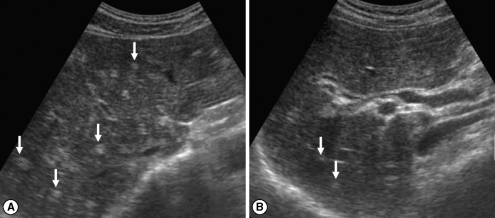

In the initial (pre-treatment) sonography of the 83 cured patients after treatment, DDIHD, IPDE, and FEFGB were found in 82 (98.2%), 42 (50.6%), and 32 (38.6%), respectively (Table 3). After treatment, DDIHD, IPDE, and FEFGB were found in 80 (96.4%), 45 (54.2%), and 17 (20.5%), respectively. DDIHD was improved in 3 (Fig. 1), aggravated in 1, and unchanged in 79 patients. IPDE was improved in 5 (Fig. 2), aggravated in 8, and unchanged in 70 patients. FEFGB was improved in 20 (Fig. 3), aggravated in 5, and unchanged in 58 patients. Neither DDIHD nor IPDE showed significant changes (P = 0.625 and P = 0.581, respectively). However, FEFGB revealed a statistically significant improvement (P = 0.004) (Table 3).